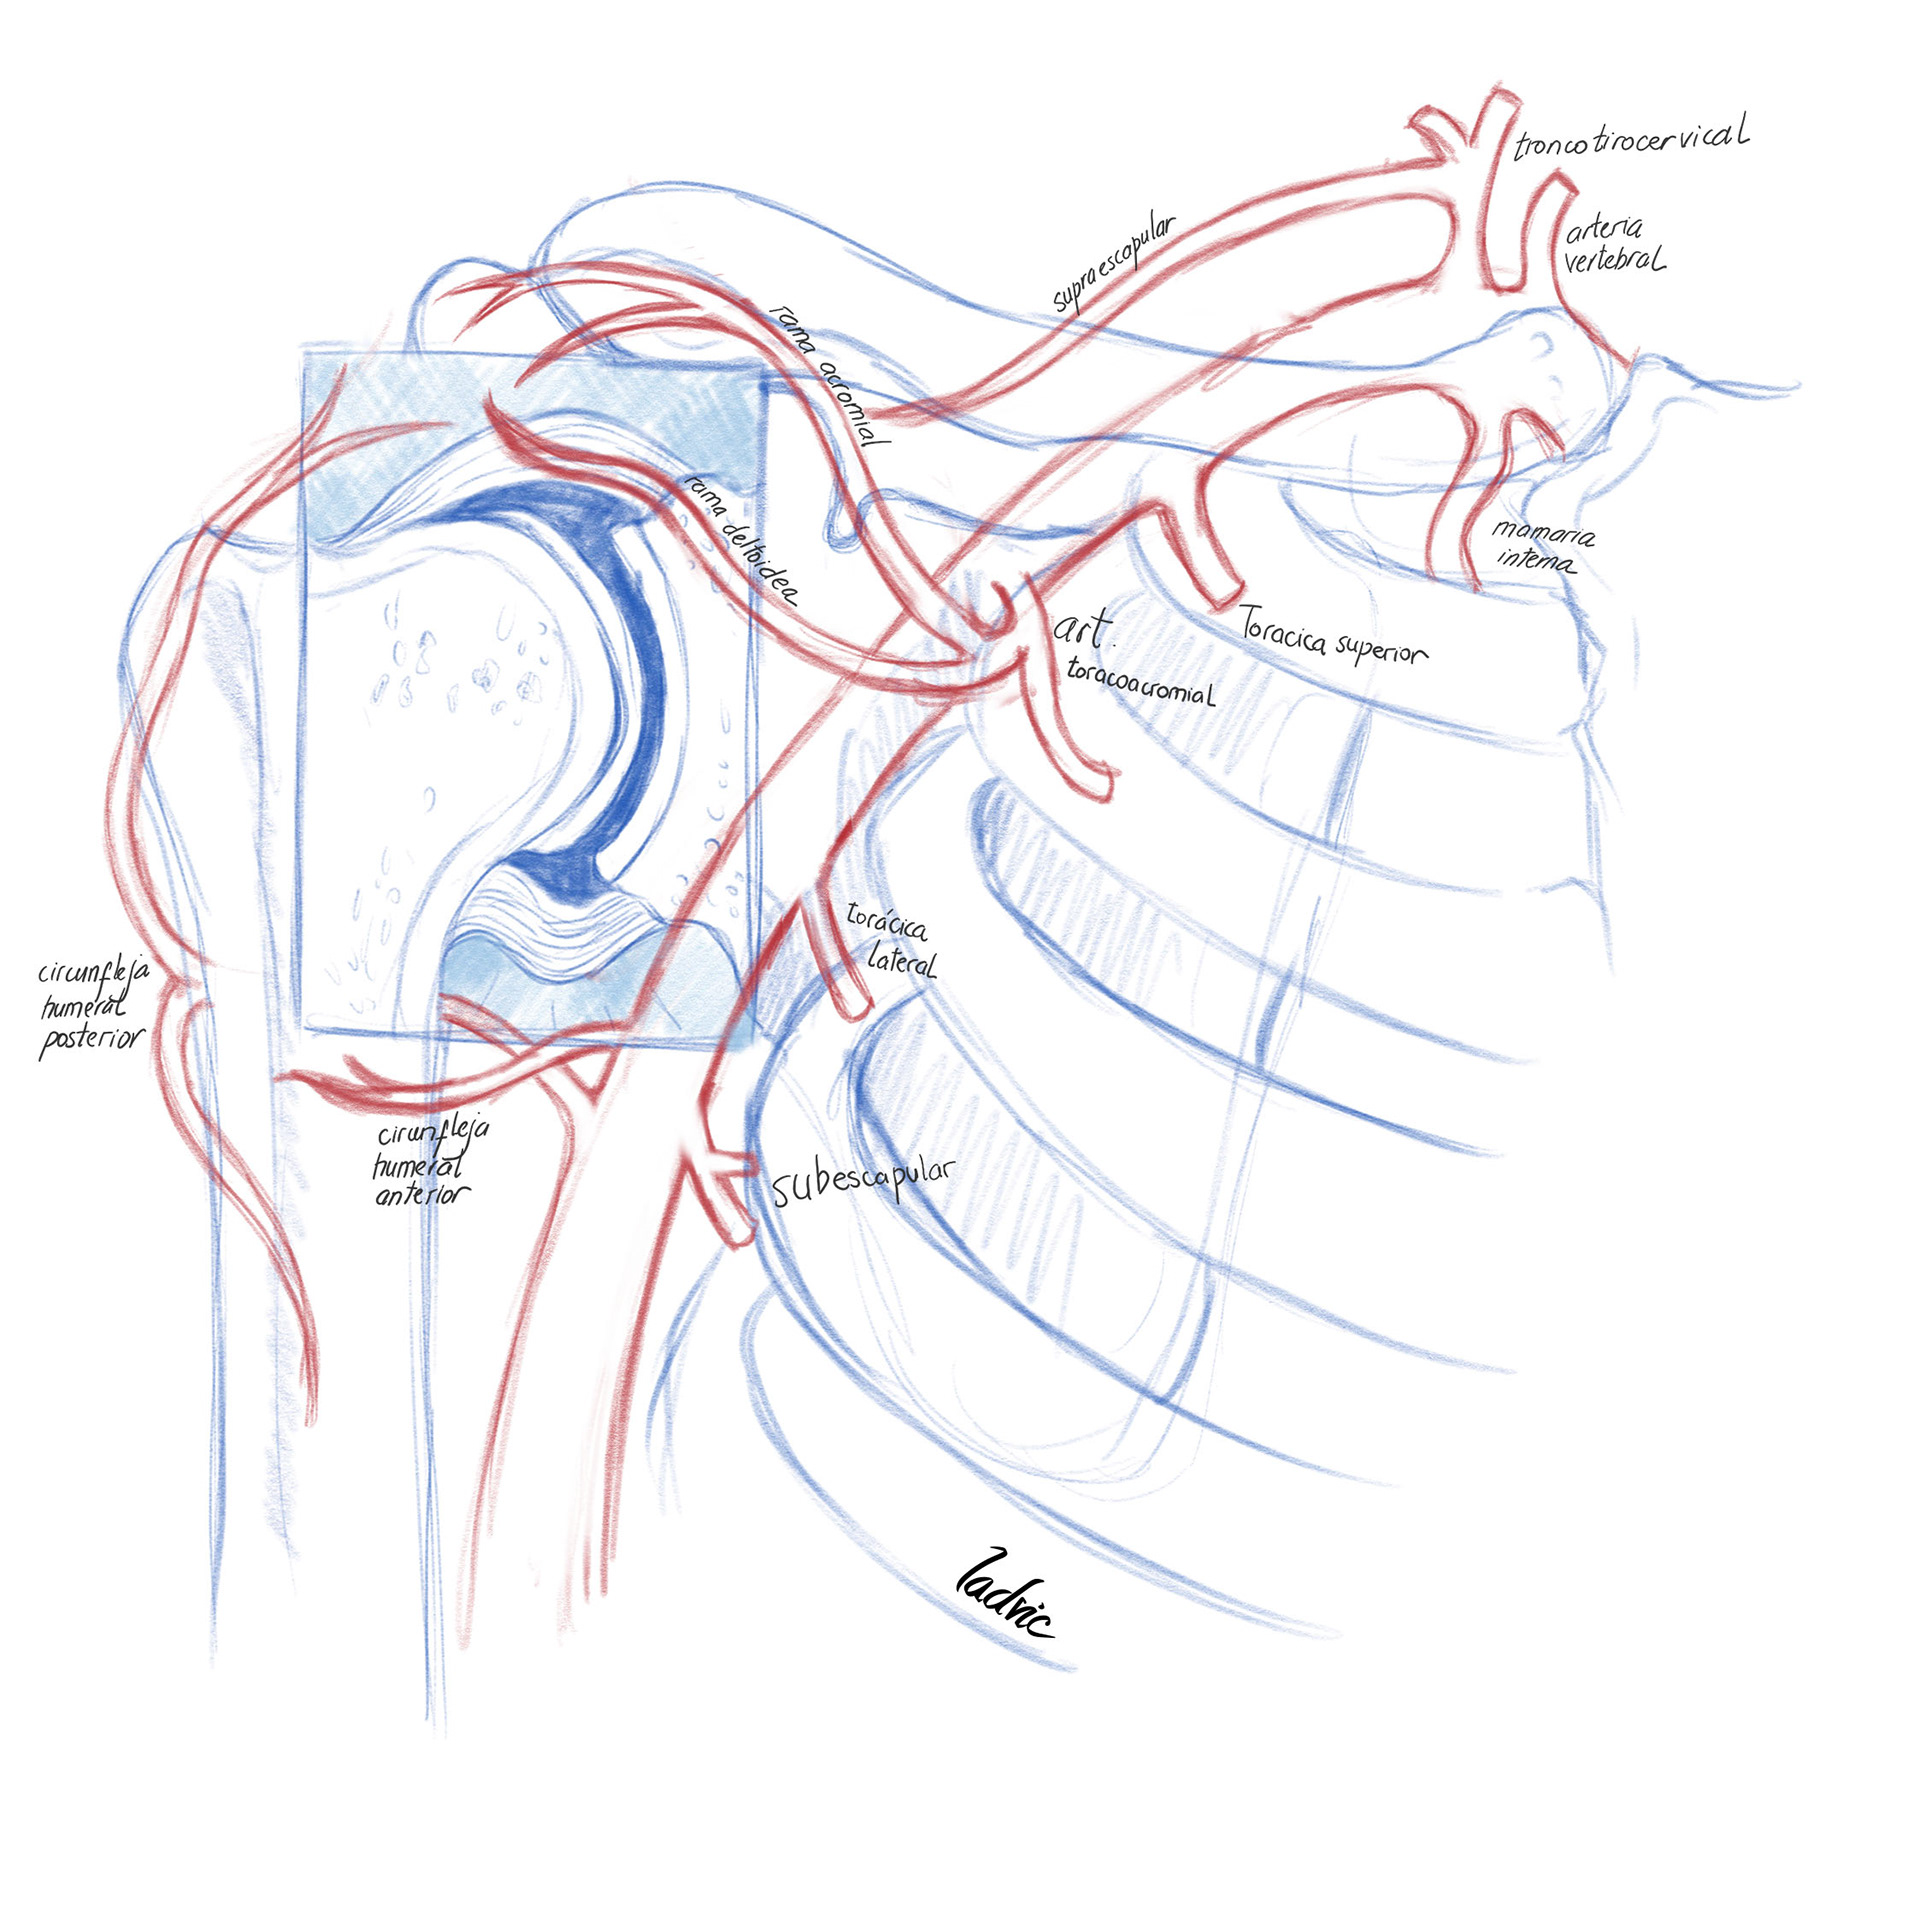

Illustration to show the vascularitation of the shoulder and diferent anatomical variants. It was made for a presentation of endovascular treatment of shoulder capsulitis.

First I draw the sketck on the iPad Pro, with the Sketchbook Software. After that, I move to Photoshop CC where, with a digital watercolour brush I painted and give the details.

I draw the anatomical variants over the same first draw but decided to desaturate the main artery so the variant could stand out.

I draw the anatomical variants over the same first draw but decided to desaturate the main artery so the variant could stand out.